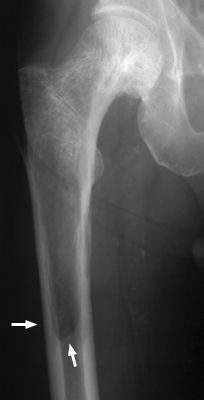

Paget's disease has three distinct phases visible radiographically: a lytic phase, a sclerotic phase, and a mixed lytic-sclerotic phase. When involvement of the lytic phase is present in a long bone, the lytic changes may advance as a V- or wedge-shaped radiolucent area, clearly demarcated from the adjacent bone. This has been likened to a blade of grass.

Right proxial femur - Click on the image for a larger version